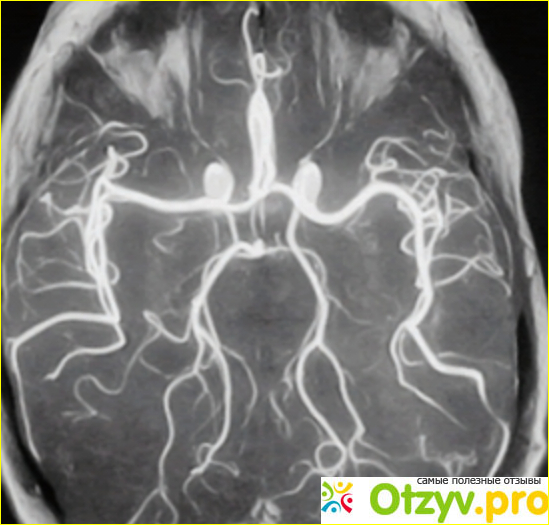

От такого диагноза даже мне стало не по себе, я стала интересоваться у врачей что же это такое, есть ли опасность для других детей. Теперь я расскажу что же мне пояснили врачи. Ли капать очень часто наблюдается у недоношенных детей. Возможно ещё в утробе у матери у ребенка было кислородное голодание, когда мозгу не хватает кислорода, то некоторые его ткани просто отмирают. Также и кислородное голодание, приводит к разжижению какого-то там вещества в головном мозге. В особой зоне риска находятся как раз недоношенные дети. Ну такое заболевание может проявиться и на более поздних сроках, а не в первые дни после рождения. Это заболевание очень сложно диагностировать. Но врачи, уделяют особое внимание недоношенным деткам. Поэтому Удалось сделать диагностику заболеваний в первые дни его жизни.

Основными симптомами являются угнетенное состояние нервной системы, а также судороги. У маленьких детей это может быть ещё и затрудненность глотания, может быть нарушена дыхательная система. К сожалению полностью вылечить лейкопатия невозможно. Потому что некоторые ткани головного мозга уже неживые, Единственное что можно сделать в этом случае это просто устранить симптомы.

Случается не только у детей. Например среди взрослых людей могут быть подвержены ему Те у кого ВИЧ, а может быть какие-то заболевания крови. В общем всё то, что снижает иммунитет, и мешает нормальному притоку крови к головному мозгу. Взрослых это также проявляется, как он маленьких детей. Это может быть нарушение координации движений, неправильная речь, может отразиться даже на зрение, иногда даже случаются приступы, похожие на эпилепсию. Естественно у взрослых Это постоянная головная боль.